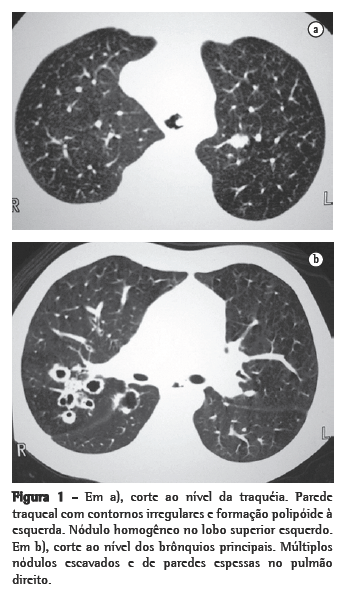

ResultadosNos 8 casos foram observadas na TC formações polipóides na traquéia. Em 1 deles, identificou-se também uma lesão em brônquio principal. Sete pacientes mostravam comprometimento do parênquima pulmonar. Em todos foram observadas lesões nodulares escavadas, com contornos internos irregulares, e paredes de espessuras variadas, com aspecto multilobulado em 6 casos, e com confluência das lesões em 5 deles (Figuras 1 a 5). Nódulos sólidos foram vistos em 6 pacientes, Em apenas 1 dos casos foram vistos níveis líquidos. As lesões predominaram nas bases em 3 pacientes, nos terços médios em 2, e em 2 não havia predomínio de distribuição. Em 1 dos pacientes, foi observada associação com massa, e em outro, com consolidação. Neste último paciente (Figura 5) foi constatada degeneração maligna em múltiplas lesões. Sinais de aprisionamento aéreo também foram observados em 1 caso. Em nenhum deles detectou-se linfonodomegalia ou derrame pleural.

A TC, particularmente com aquisição volumétrica (espiral), é superior às radiografias de tórax no reconhecimento de nódulos ainda pequenos, nas fases iniciais de disseminação pulmonar, por sua melhor caracterização e visualização de vegetações nodulares traqueobrônquicas. Os achados tomográficos incluem estreitamento nodular, focal ou difuso, da via aérea. Os nódulos crescem na superfície mucosa, e sua extensão intraluminar é melhor avaliada por TC.(3) São alterações facilmente correlacionadas à doença quando se dispõe da história clínica de papilomatose.(4) Outros achados relacionados à obstrução das vias aéreas e/ou infecções associadas são atelectasias, consolidações, aprisionamento aéreo e bronquiectasias.(2-4) Na nossa casuística, formações polipóides na traquéia foram observadas em todos os exames tomográficos. Sete pacientes mostravam comprometimento do parênquima pulmonar, caracterizado por lesões nodulares escavadas, com contornos internos irregulares, e paredes de espessuras variadas, com aspecto multilobulado e tendendo à confluência. Nódulos sólidos foram vistos em 6 pacientes. Em nenhum deles detectou-se linfonodomegalia ou derrame pleural.